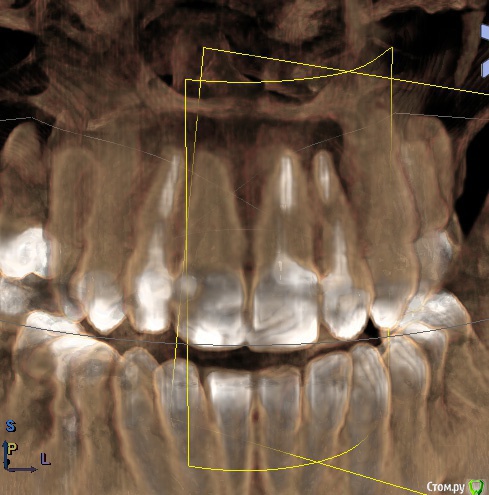

Ankazabolevshaya Опубликовано 28 мая, 2016 Поделиться Опубликовано 28 мая, 2016 Здравствуйте, уважаемые врачи! Очень сильно нуждаюсь в вашей помощи. В 2013 мне лечили два передних зуба (клык и передний). Пломбировали каналы, но коронки не ставили. Этой зимой я почувствовала боль в передних зубах в районе челюсти. Раздражение в дёснах. Резь. Потом вылез какой-то пупырь на десне. Я думала, что это стоматит. Не верила тем, кто мне говорил про нужность обзорного снимка. Признаю свою глупость. Теперь, после КТ оказалось что у меня сломаны эти каналы, а под левым клыком пустота. А пупырь, как мне сказали - это выход свища.Мне предложили зуб удалять. Как-то восстанавливать эту пустоту. Потом делать имплантацию. Есть ли сегодня технологии, позволяющие восстанавливать это пространство под зубом без его удаления, с последующей коронкой на него? И ещё один вопрос: могло ли все это случится из-за какой-нибудь заразы, занесенной во время лечения этих двух зубов в 2013г. ? Так же был момент ранения слизистой левой ноздри, как раз над свищем, который на десне. Просто очень часто слизистая иссыхала в одном месте и я травмировала слизистую. Буду очень благодарна за ответ. От меня в клинике ждут решения, а я переживаю, что улыбка испортится с искусственным зубом. Зуб этот свой очень люблю. Анна. Ссылка на комментарий

red_butler Опубликовано 28 мая, 2016 Поделиться Опубликовано 28 мая, 2016 Спасибо! Можете пояснить, Вы думаете, что зуб можно спасти? если судить только по снимкам, то да 1 Ссылка на комментарий

red_butler Опубликовано 29 мая, 2016 Поделиться Опубликовано 29 мая, 2016 а скажите, как по Вашему, это киста прикорневая? Или челюсть разрушена? Нужно восстановление челюсти? это не важно и корень ведь сломан, поставить под коронки всё равно можно? перелома не увидел И еще последнее, как Вы относитесь к процедуре - депофорез? В моём случае стоит в эту торону смотреть? бесполезно 2 Ссылка на комментарий